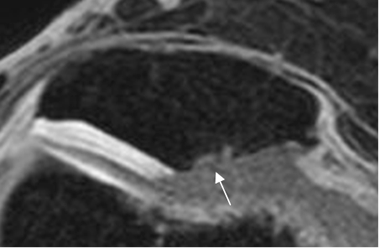

Fig 166. Condromalacia patelar grado 2.

A: RM axial en T2 y B: RM axial en 3D T1 STIR. Erosión del cartílago articular a nivel del vértice, menor del 50%.